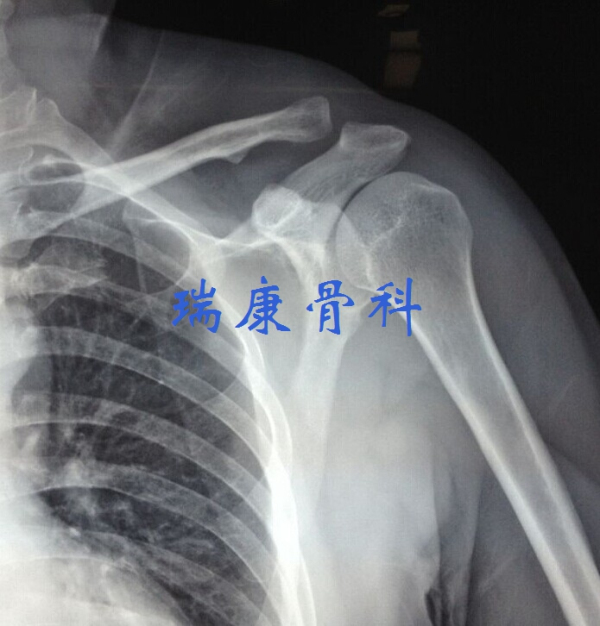

• 肩膀痛不等于“肩周炎”——微创外科技术系列报道(一)

肩膀痛不等于“肩周炎”——微创外科技术系列报道(一)

在我国,老百姓有了肩部疼痛和活动受限就自认为患了肩周炎,甚至部分骨科医生也常常用肩周炎笼统地诊断肩部病痛。其实肩膀痛完全不等于...